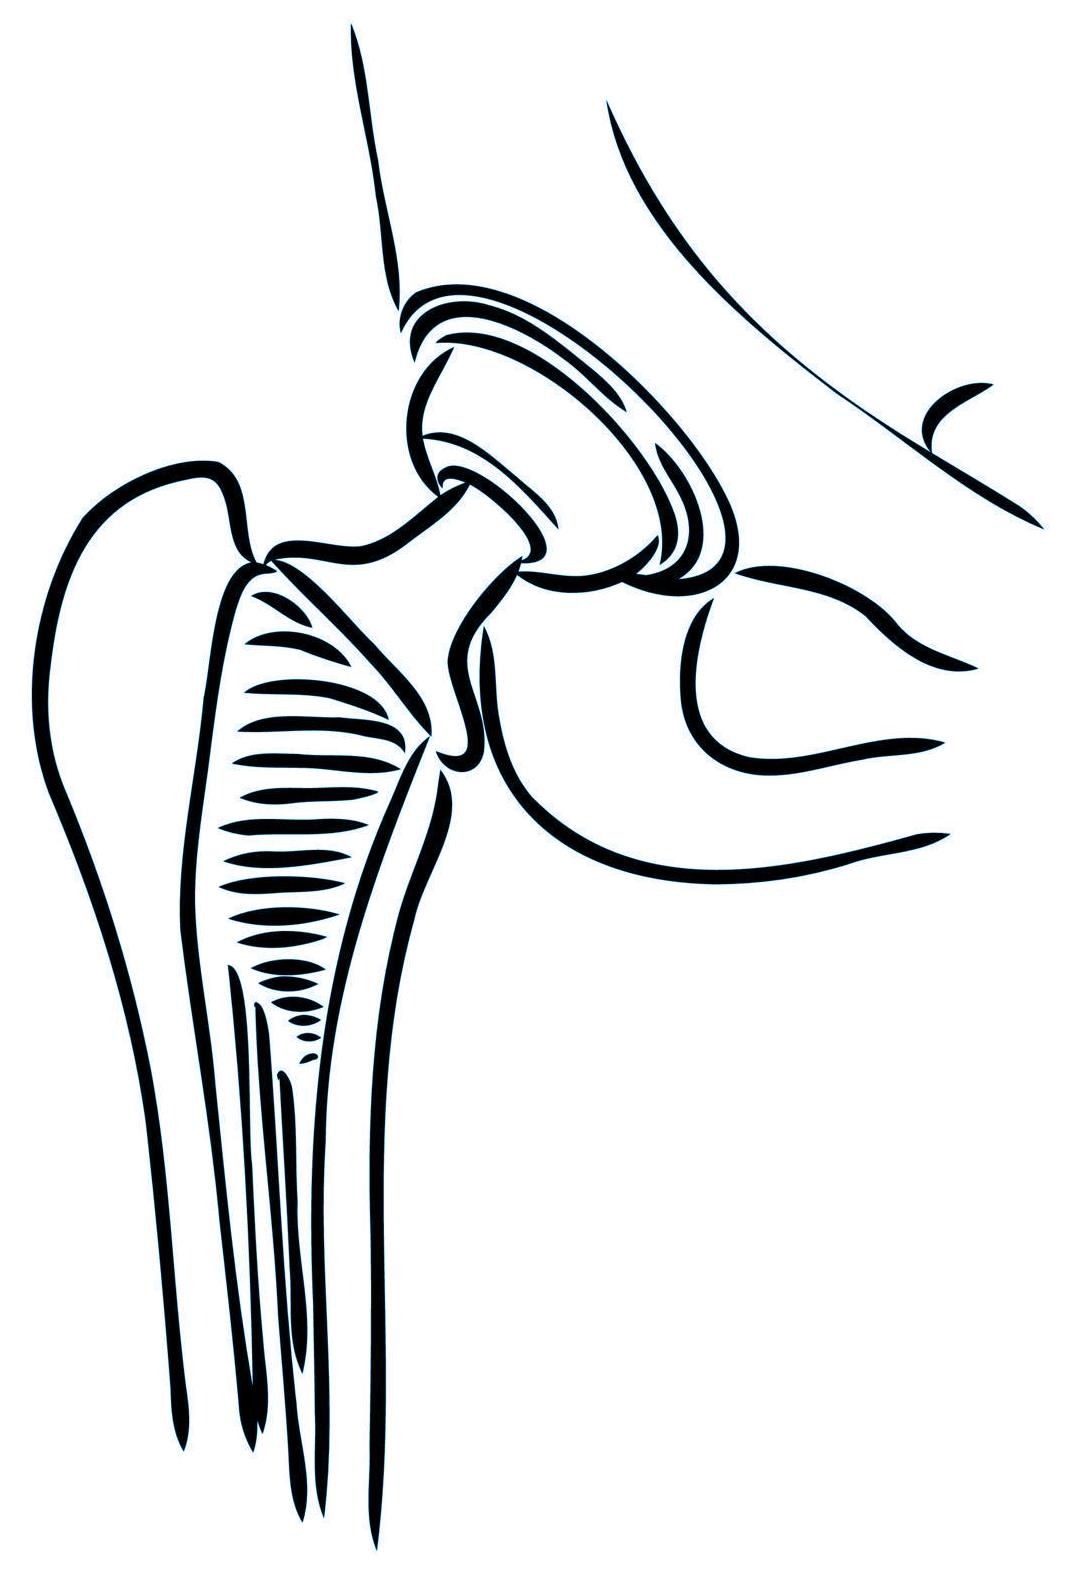

Cirugías de Cadera

Reemplazo de cadera

Fracturas en adultos mayores